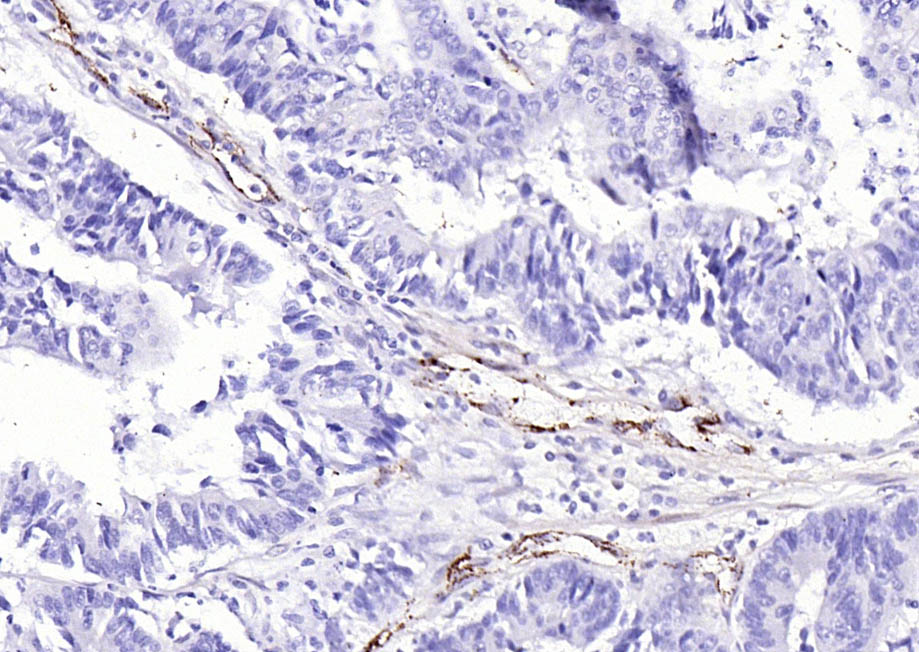

Cancer > Invasion/microenvironment > Angiogenesis > Angiogenic growth factors

Cardiovascular > Angiogenesis > Endothelial Cell Markers

| IHC-P | Human, Rat | Mouse | 1:100-500 |